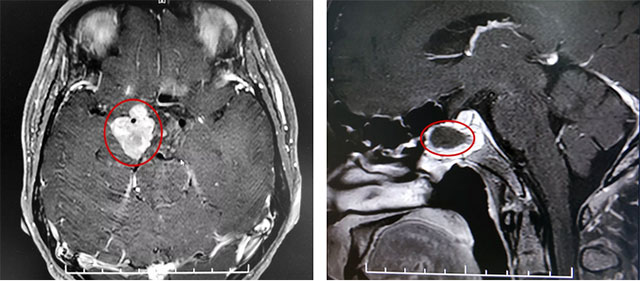

▲ 巨大垂體瘤殘余

患者蔡先生(化名)因持續(xù)頭痛、視力下降被查出是垂體無功能巨大腺瘤,腫瘤大小超過3cm。在杭州一家醫(yī)院做了經(jīng)蝶竇垂體瘤切除手術(shù)后,由于術(shù)后腫瘤殘余較多,出現(xiàn)頭痛情況,視力較術(shù)前未見明顯改觀,左側(cè)視力0.12,右側(cè)視力0.1。后慕名來到上海藍(lán)十字腦科醫(yī)院。

李士其教授指出,經(jīng)鼻蝶手術(shù)主要用于腫瘤位于鞍內(nèi)者,對于鞍內(nèi)、鞍上均有生長的巨大垂體瘤,考慮聯(lián)合入路手術(shù),部分患者也可以考慮多次經(jīng)鼻蝶手術(shù)。

該巨大垂體腺瘤患者鞍上區(qū)域殘余腫瘤偏向右側(cè),只能通過開顱手術(shù)切除。

在充分準(zhǔn)備并征得家屬同意后,李士其教授在吳治群博士、黃秀夫醫(yī)生協(xié)助下為患者行開顱手術(shù),經(jīng)翼點(diǎn)入路將殘余約2.5cm*2cm*2cm大小腫瘤切除。